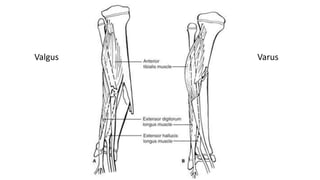

• 60 % develop varus angulation within 1st 2 weeks of injury

• Valgus malalignment

Valgus Varus